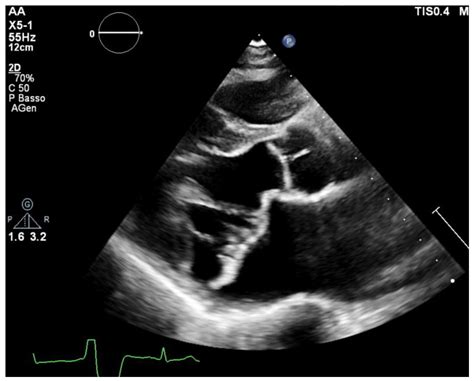

Physicians typically diagnose a heart valve issue through a physical examination, where a doctor listens for a “heart murmur” using a stethoscope. This abnormal sound is often the first clue that blood is not flowing perfectly through the valves. To confirm a mild leaky heart valve, your doctor will likely use advanced imaging.

Echocardiogram Uses ultrasound waves to create real-time images of the heart valves and blood flow.